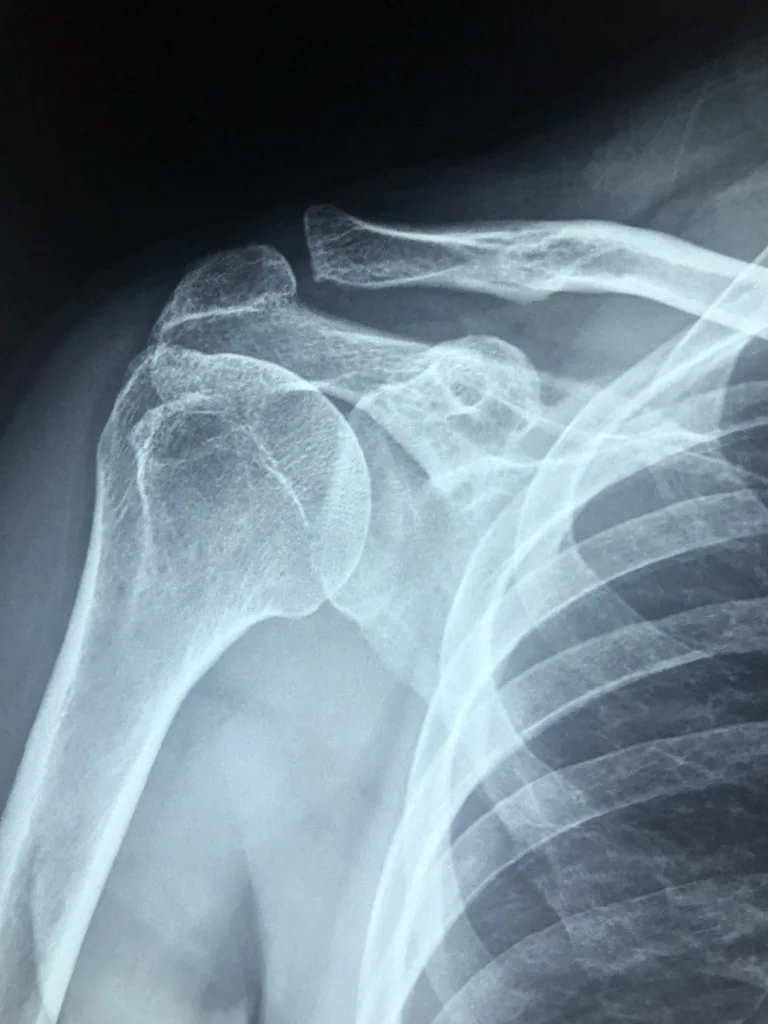

According to reports, Meaux went to the emergency room Christus St. Mary Hospital on October 2, 2007 and reported symptoms of severe chest pains. Dr. Michael Peterson performed tests on the woman and incorrectly diagnosed and treated the woman for irregular breathing and released her from the hospital despite an irregular EKG result of the two taken. While the doctor did prescribe Captopril, a drug that can help with heart problems and increase changes of survival after a heart attack, he did not keep her for observation.